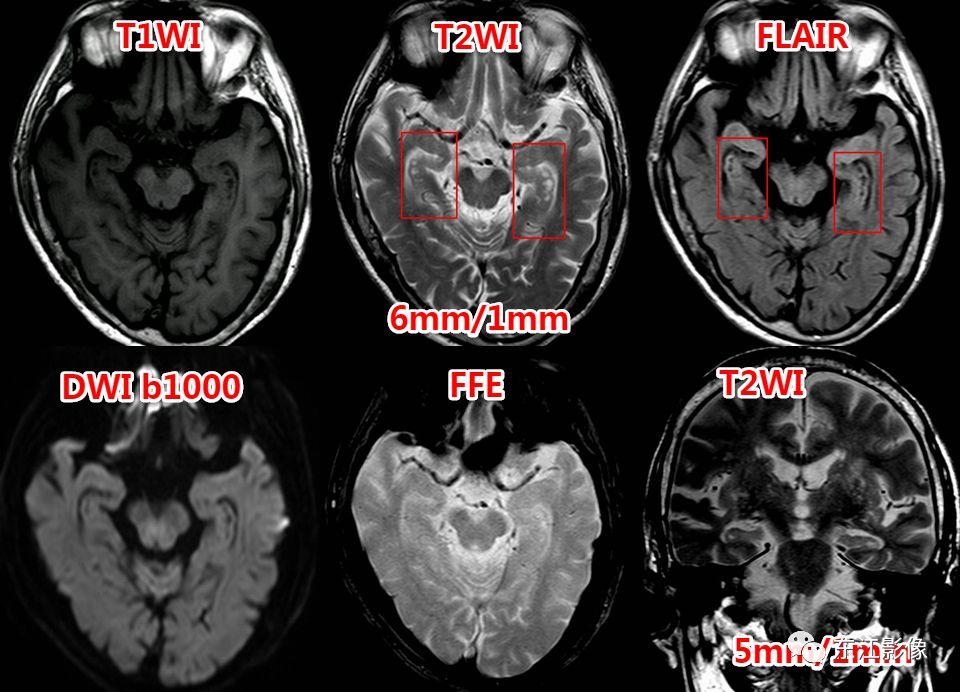

2. 静脉窦内扩大的蛛网膜颗粒

- 蛛网膜在硬脑膜构成的静脉窦附近形成许多绒毛状突起,突入静脉窦内,形成静脉窦内蛛网膜颗粒。

- 随着头颅MRI的广泛使用,静脉窦内扩大的蛛网膜颗粒“变得”非常常见。

- 不熟悉的话,容易误诊为异常。

- 以横窦常见(横断面图像最容易被发现的缘故),其次为上矢状窦,直窦、乙状窦少见,海绵窦罕见。

- CT平扫,呈稍高密度背景内低密度充盈缺损。

- MRI T1WI为低信号,稍高于脑脊液信号;T2WI为高信号,FLAIR多为低信号,稍高于脑脊液信号,较大的其内可见絮状稍高信号;增强多无强化,较大的其内可见点、线状强化灶。MRV上均呈附壁状充盈缺损。

- 极少数静脉窦内扩大的蛛网膜颗粒可能会引起静脉窦狭窄,DSA实时压力测量是确诊工具。

右侧横窦扩大的蛛网膜颗粒。

左侧横窦扩大的蛛网膜颗粒。

上矢状窦、直窦多发扩大的蛛网膜颗粒,薄层T2WI切线面显示更佳。